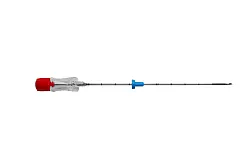

Jehla do bioptického děla PALIUM®

PALIUM® Needle je jednorázová jehla typu tru-cut, navržená pro bezpečný a precizní odběr bioptických vzorků měkkých tkání. Díky atraumatickému hrotu typu „Menghini“ a centimetrovým značkám umožňuje přesný a kontrolovaný odběr. Je plně kompatibilní s automatickými pistolemi a díky echogennímu značkovači je vynikajícně viditelná pod ultrazvukem. Co oceníte na jehle PALIUM® Needle: Precizní odběr vzorků Jednoduchá kontrola hloubky Vylepšená viditelnost Spolehlivá kompatibilita Jednorázové použití